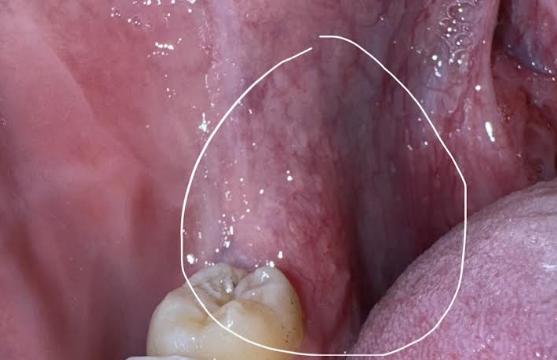

Bác sĩ cho em hỏi, đoạn chỗ lợi cạnh răng hàm cuối của cả 2 bên hàm dưới bị như này là sao vậy ạ? Em bị cũng một thời gian, dùng lưỡi chà vào cảm giác cứng cứng, dưới lớp da hơi nhô lên ạ.

Vị trí mà em miêu tả là vị trí của răng khôn. Răng khôn là tên gọi chung dành cho những chiếc răng hàm mọc cuối cùng ở mỗi bên hàm, hay còn được gọi với tên khác là răng số 8. Những chiếc răng này không mọc ở trẻ nhỏ hay khi ở răng đã thay mà nó xuất hiện cuối cùng, thường ở những người từ 18 tuổi trở lên. Được gọi là răng khôn bởi vì chúng mọc khi con người đã trưởng thành.

Em nên khám chuyên khoa răng hàm mặt, chụp phim X-quang răng để kiểm tra xem răng khôn này có tiềm ẩn nguy cơ mọc lệch gì hay không, em nhé.